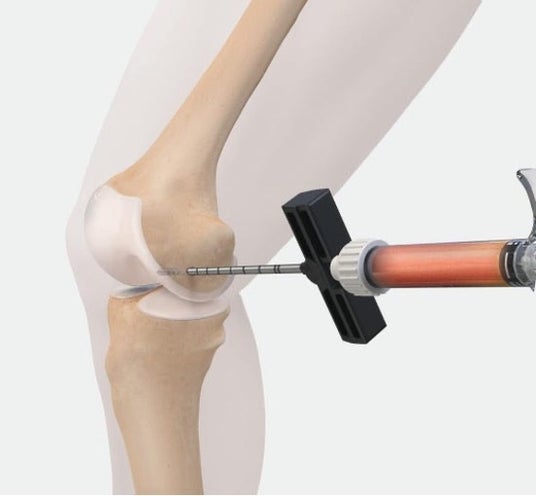

骨の中にPRPや細胞などの生物由来材料を専用の医療機器で注入し骨の治癒や再生を促す

IOBPはBML(Bone marrow lesion、骨髄異常陰影)に対する治療であり、体への負担が少ない手術です。骨の中にPRPや細胞などの生物由来材料を専用の医療機器で注入し、骨の治癒や再生を促します。

IOBPは骨の中に「Angel cPRP/BMCシステム」などで調整したPRP(多血小板血漿)やBMC(濃縮骨髄液)などの生物由来材料を専用の医療機器で注入し、骨の治癒や再生を促す治療です。